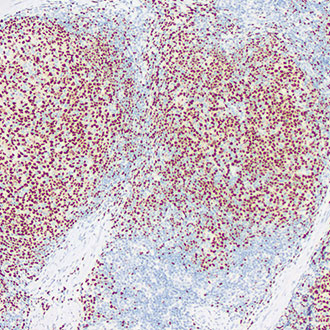

EZH2

EZH2 -